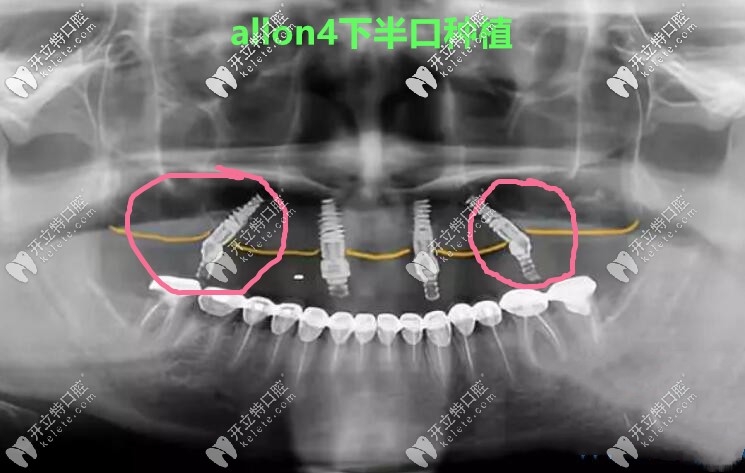

做allon4下半口種植牙真人案例CT照↓↓↓

做allon4下半口種植牙真人案例CT照

張海波院長(zhǎng)說(shuō),它倆明顯的區(qū)別就是,allon4/6有2顆植體是斜著的,因?yàn)楸荛_(kāi)了神經(jīng)管和上額竇孔腔,所以主要針對(duì)的是那些牙槽骨非常糟糕,無(wú)法常規(guī)種植的人。

allon4/6技術(shù)對(duì)醫(yī)生要求很高,會(huì)用到3D數(shù)字化導(dǎo)板,費(fèi)用在一萬(wàn)以上,所以,總體價(jià)格會(huì)貴些。